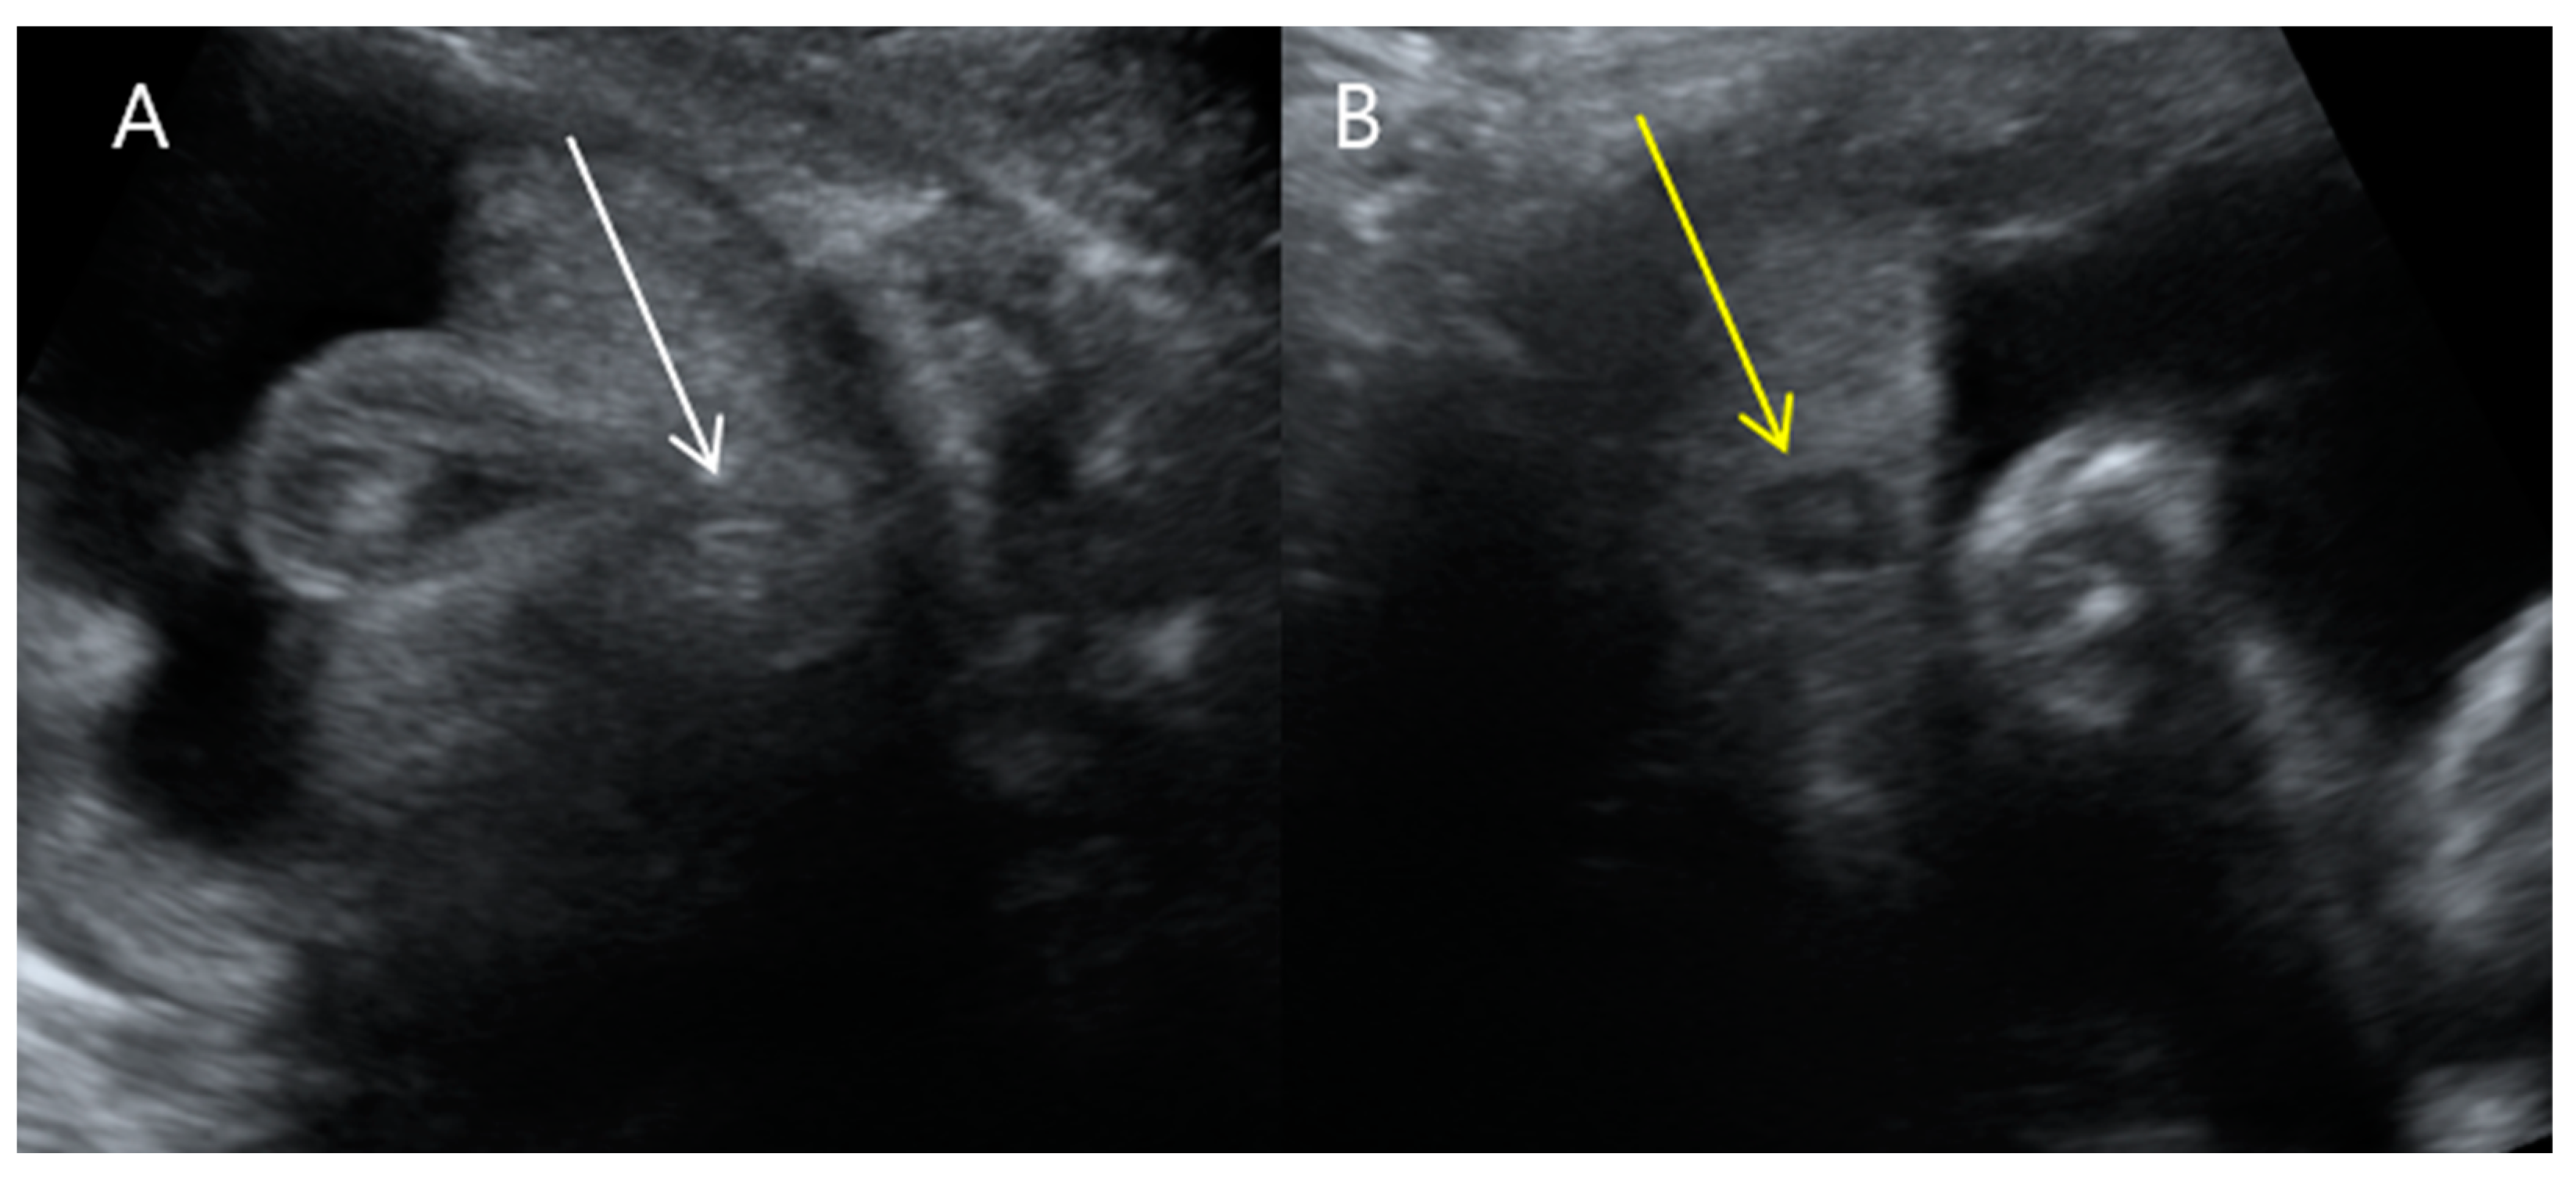

On transventricular view, both of fetus A’s lateral ventricles were severely dilated at 31.0 mm and 29.5 mm, resulting in cortical mantle thinning (Figure 1). Fetus A’s third ventricle was dilated to 5.8 mm, but no other brain abnormalities were found.

Figure 1. Transventricular view of the twin fetuses on ultrasound examinations at 31 + 3 weeks gestation. (A,B) Fetus B, a healthy female with normal-sized atrial widths of both left and right lateral ventricles (Va and Vp were <10 mm) (C,D) Fetus A, a male with severe ventriculomegaly; left and right (Va, Vp) at 31.16 mm and 29.59 mm, respectively. Note that in Va and Vp, the abbreviation ‘a’ indicates the closer side to the ultrasound probe (the anterior side of the mother), and the abbreviation ‘p’ presents the farther side from the ultrasound probe (the posterior side of the mother).